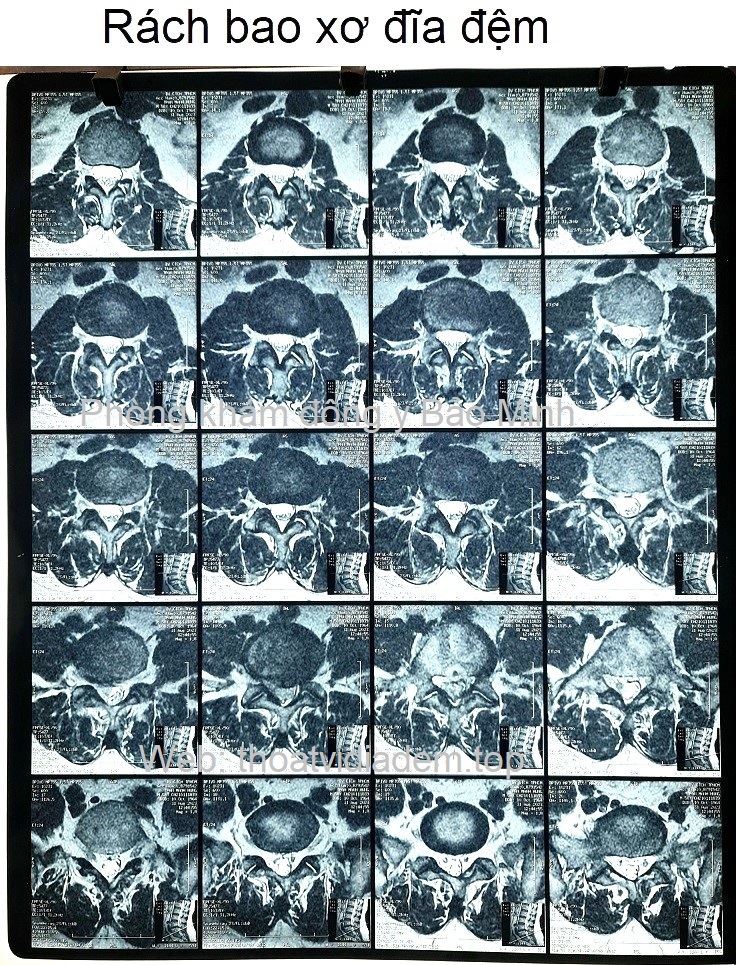

Thoát vị đĩa đệm, rách vòng xơ, chèn rễ L3 trái, chèn rễ L5 phải.

Xẹp L2 và trượt L2 ra sau độ 1

Lồi đĩa đệm tầng L1-L2, L5-S1, ép mặt trước bao màng cứng, chưa chèn ép rễ.

Lồi kèm thoát vị đĩa đệm tầng L2-L3, di trú xuống dưới ở ngách bên trái, ép mặt trước bao màng cứng, làm hẹp ngách bên trái, chèn rễ L3 trái.

Lồi đĩa đệm tầng L3- L4, ép mặt trước bao màng cứng, làm hẹp ngách dưới lỗ liên hợp hai bên, chưa chèn rễ.

Thoát vị đĩa đệm dạng trung tâm tầng L4-L5, có rách vòng xơ, có mảnh rời di trú xuống dưới ở ngách bên phải, ép mặt trước bao màng cứng, chèn ép rễ L5 phải. Thoái hóa cột sống thắt lưng.

Thoát vị đĩa đệm, rách vòng xơ, chèn rễ L3 trái, chèn rễ L5 phải.Lồi kèm thoát vị đĩa đệm tầng L2-L3, di trú xuống dưới ở ngách bên trái, ép mặt trước bao màng cứng, làm hẹp ngách bên trái, chèn rễ L3 trái. Thoát vị đĩa đệm dạng trung tâm tầng L4-L5, có rách vòng xơ, có mảnh rời di trú xuống dưới ở ngách bên phải, ép mặt trước bao màng cứng, chèn ép rễ L5 phải. Thoái hóa cột sống thắt lưng.❮ đọc tiếp ❯